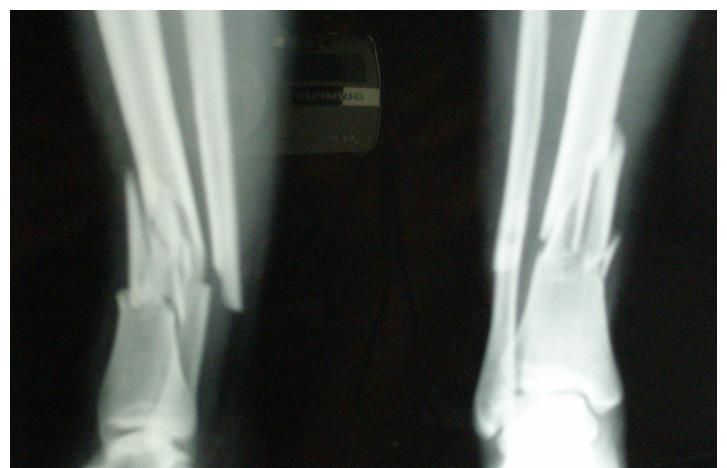

经过检查,刘线上患上了骨质疏松症,而且因为脊无纺布面粉袋生产电话/微信:15838231350椎被摔骨折,直接导致下肢瘫痪,永远站不起来了。在医生对其生活习惯的了解后,明白了病因所在。

4、骨密度下降,抗冲击力下降,轻轻碰撞或摔倒就会出现骨折;